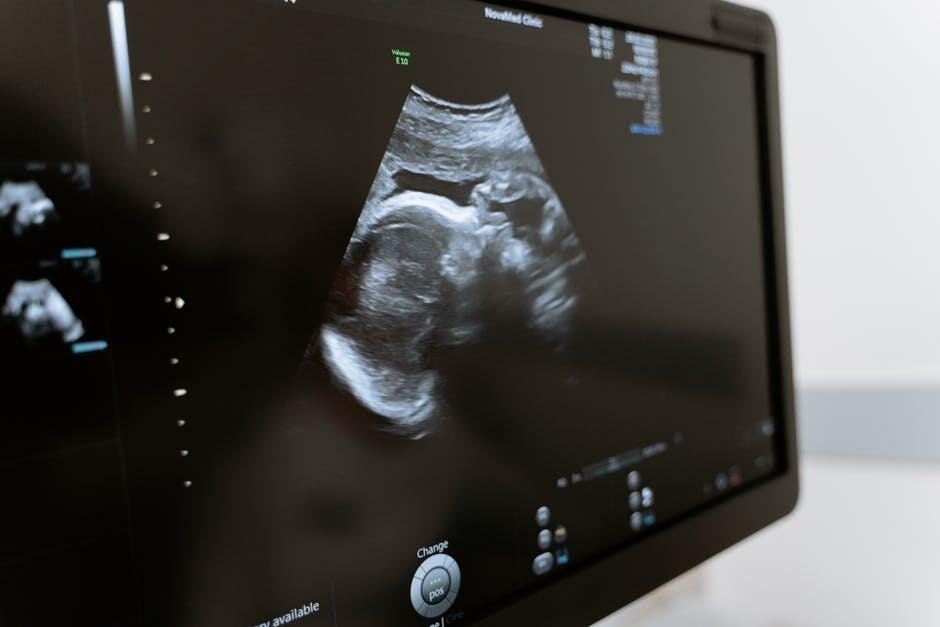

Have you ever wondered what your baby looks like at 13 weeks? This question is on the minds of many expectant parents.

A 13 week sonogram offers a sneak peek into your baby’s development. It’s an exciting time to connect with your little one. Seeing tiny fingers and toes can make the journey feel real. In this article, we’ll help you understand these fetal development images.

Experiencing the early stages of your baby’s development can be heartwarming and exciting. A 13 week sonogram provides a precious glimpse into this remarkable journey. It’s a moment that many parents cherish forever, as they begin forming a bond with their little one.